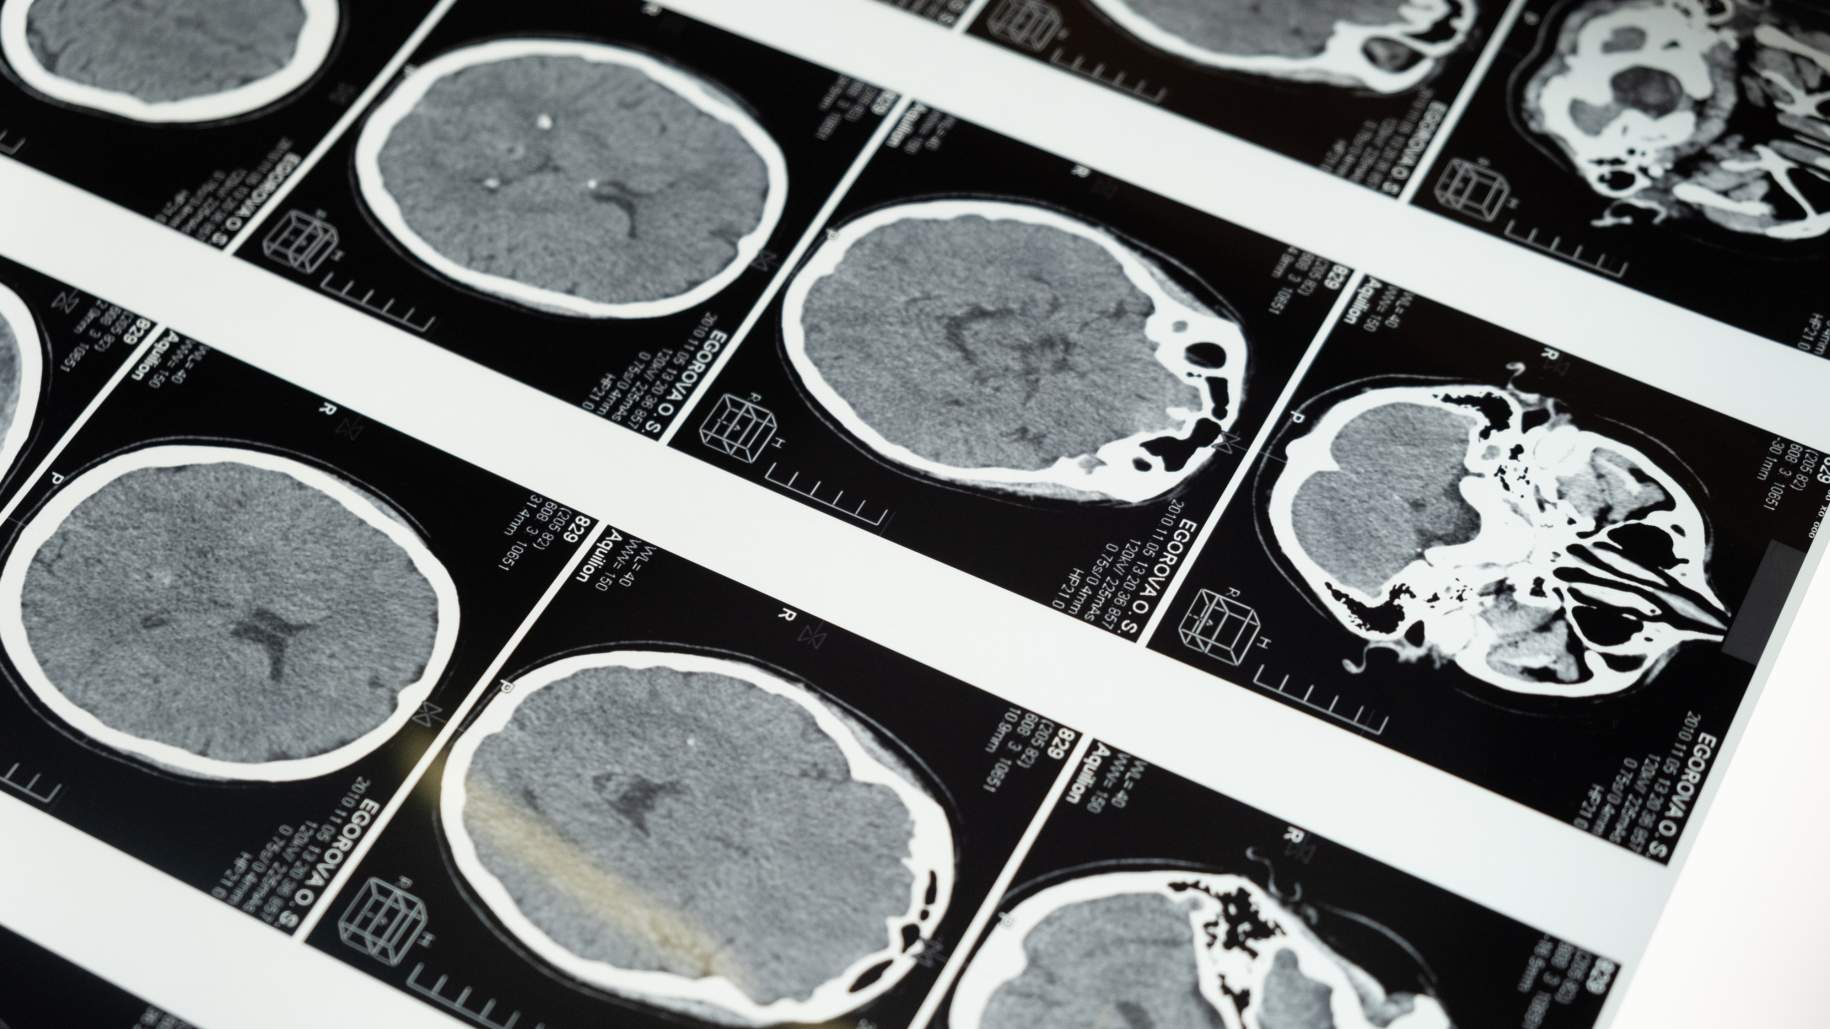

- Pruebas de imágenes: los craneofaringiomas pueden ser visibles con pruebas de imágenes como resonancia magnética y tomografía computarizada.